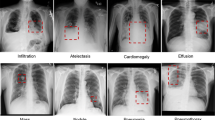

Textural properties of normal and tuberculosis posterior-anterior chest radiographs were looked into in this investigation. The proposed computerized scheme segmented the lung field of interest using a user-guided snake algorithm and extracted the corresponding pixel data. For both normal and tuberculosis radiographs, the grayscale intensity distribution within the region of interest was analyzed to study their respective characteristics, and fed to classifiers for automated classification. Statistically the tuberculosis infected radiographs manifested a higher variance, third moment, entropy and a lower mean value in their intensity distributions, compared to their normal peers. The greater disparities between a particular radiograph and the confidence interval determined by our normal groups on some of the features were observed to be related to the level of haziness at the upper lobe. Lastly, the C4.5 (a decision tree based classifier)-adaboost achieved an accuracy of 94.9% in normal-tuberculosis classification. An integrated index, called tuberculosis index (TI), is proposed based on texture features to discriminate normal and tuberculosis chest radiographs using just one index or number. We hope this TI can be used as an adjunct tool by the radiographers in their daily screening.